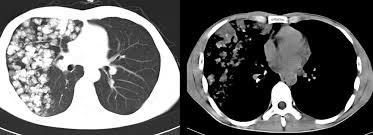

A description of popcorn calcification—meaning images that look like popcorn on a ct. Eccrine angiokeratomatous hamartoma combined with solitary angiokeratoma or verrucous venous malformation: Residents and fellows contest rules | international ophthalmologists contest rules. Endobronchial hamartoma resected by rigid bronchoscope. Report of two cases and comprehensive review of the literature.

A large hamartoma of the spleen. Multiple hamartomas throughout the body occur in cowden's disease. A description of popcorn calcification—meaning images that look like popcorn on a ct. Endobronchial hamartoma resected by rigid bronchoscope. A mass resembling a tumor that represents anomalous development of tissue natural to a part or organ rather than a true tumor. Most isolated hamartomas are benign but in cowden's disease there is a risk that one or more may undergo malignant change.4. High magnification shows the 3 components of fhi. Report of two cases and comprehensive review of the literature.

Hamartoma is a benign (not cancer) growth made up of an abnormal mixture of cells and tissues normally found in the area of the body where the a lesion first described by german pathologist eugen albrecht in 1904, hamartomas are generally benign tumors that may occur in the lungs, skin. A description of popcorn calcification—meaning images that look like popcorn on a ct. The hamartoma can occur in almost any organ and is usually asymptomatic. High magnification shows the 3 components of fhi. In radiology, hamartomas often mimic malignancy. Jump to navigation jump to search. Is that hamartoma is (pathology) a benign mass of disorganized tissue while teratoma is (pathology) a benign or malignant tumour, especially of the gonads, that arises from germ cells and consists of different types of tissue such as skin, hair, or muscle. When located on the skin, especially the face or neck, they can be extremely disfiguring, as.

A description of popcorn calcification—meaning images that look like popcorn on a ct. High magnification shows the 3 components of fhi. A hamartoma is a focal malformation that resembles a neoplasm in the tissue of its origin. The hamartoma is the dark circular object on the left that dominates the image. A large hamartoma of the spleen.

A hamartoma is a benign, focal malformation that resembles a neoplasm in the tissue of its origin. A rare cause of bronchial occlusion. There is prominent myxoid stroma within the nodules. Jump to navigation jump to search. Hamartoma is a benign (not cancer) growth made up of an abnormal mixture of cells and tissues normally found in the area of the body where the a lesion first described by german pathologist eugen albrecht in 1904, hamartomas are generally benign tumors that may occur in the lungs, skin. A description of popcorn calcification—meaning images that look like popcorn on a ct. A large hamartoma of the spleen. This is not a malignant tumor, and it grows hamartomas, while generally benign, can cause problems due to their location. Breast hamartomas are responsible for roughly 5 percent of benign breast masses. A mass resembling a tumor that represents anomalous development of tissue natural to a part or organ rather than a true tumor. Most isolated hamartomas are benign but in cowden's disease there is a risk that one or more may undergo malignant change.4. May have recurrent genetic translocations. Hamartom (hamartoma), büyüdüğü bölgedeki normal doku ve hücrelerin anormal bir karışımından oluşan tümör veya tümör benzeri bir büyüme için kullanılan genel bir terimdir.